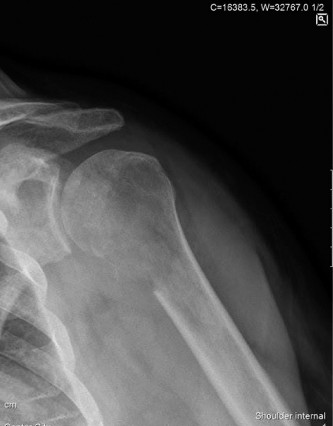

A 61-year-old female with several months of deep pain in the right shoulder is referred to you by her primary…

A left-hand-dominant, 66-year-old female is sent to your office for shoulder pain, possibly a rotator cuff te…